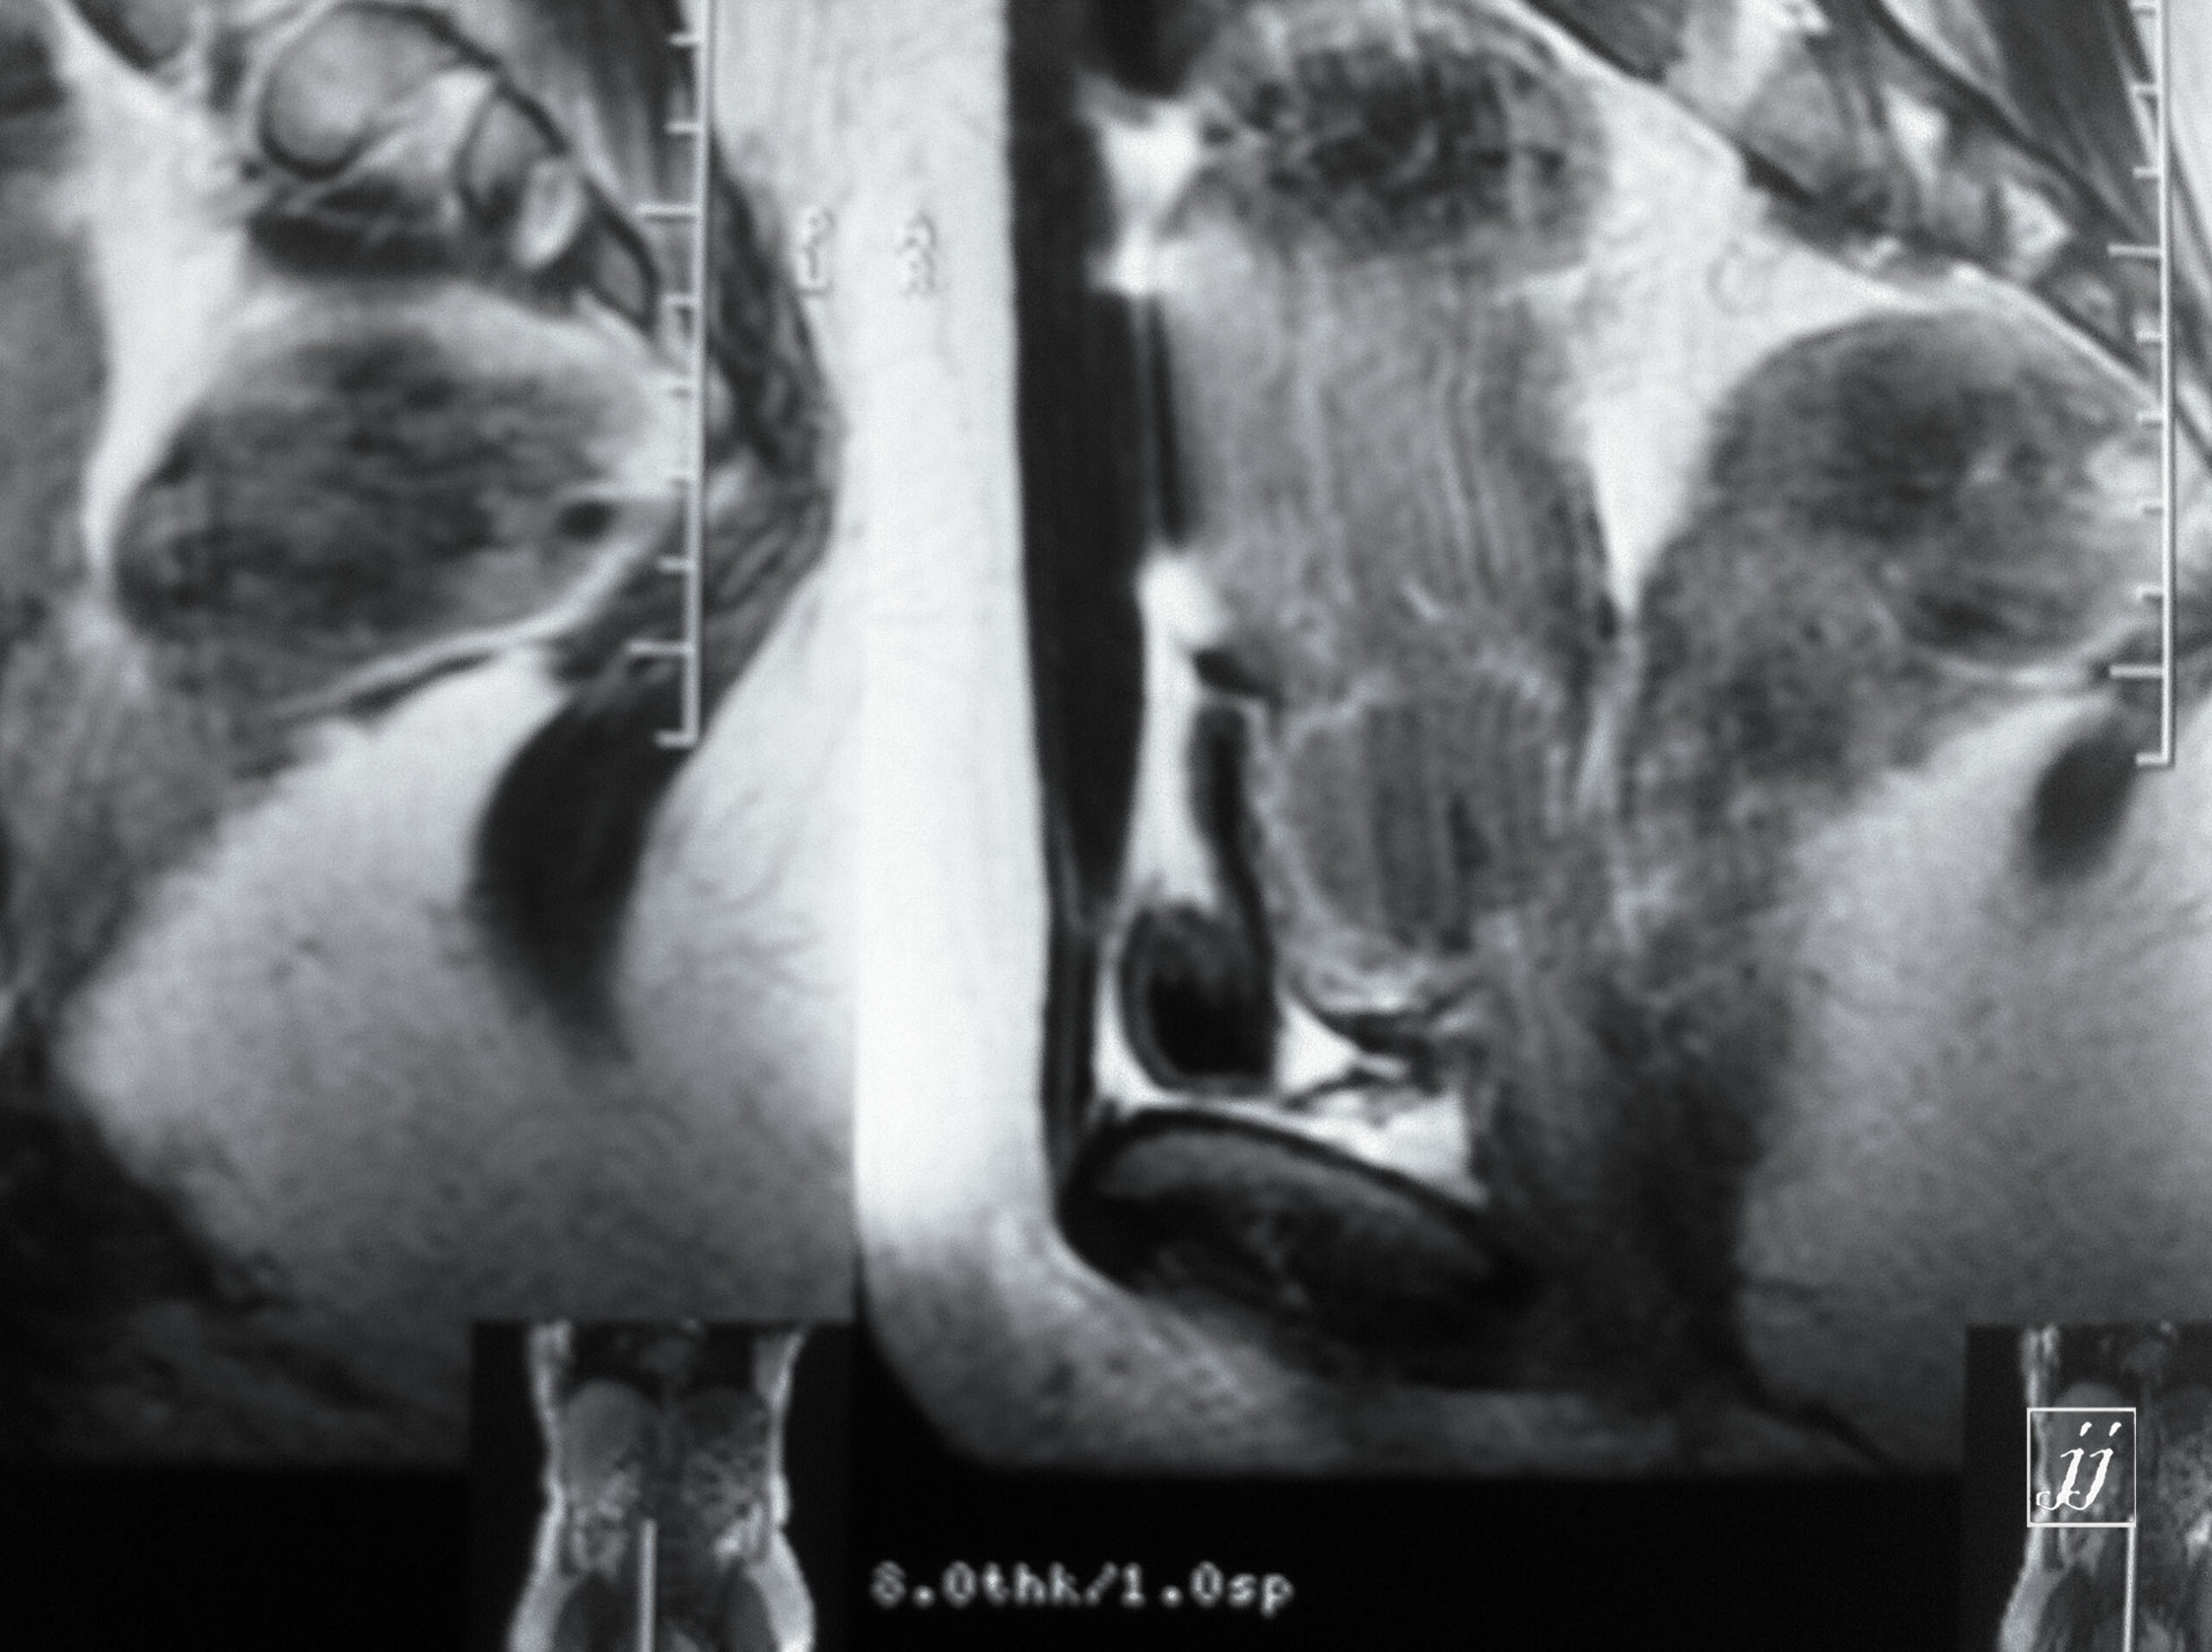

Abdomen- mass lesion posterior to UB and uterus location (6)